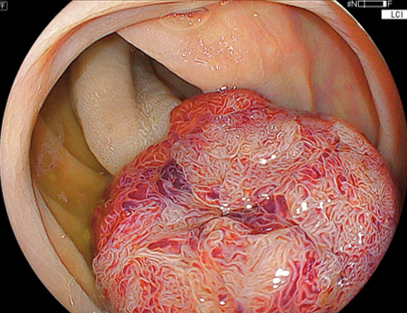

先ほどの反対側の観察では、不整な微細表面構造が

認められます。よって術前診断では高異型度腺腫

(こういけいどせんしゅ)~粘膜内癌(ねんまくないがん)

を想定しました。

ここで、治療に対して大きな支障となるのが、大型腫瘍

を栄養するための動静脈がこの茎部(けいぶ:くきのこと)

には存在しているため、術中出血・後出血(こうしゅっけつ)

のリスクは、平坦な病変よりも、高いです。